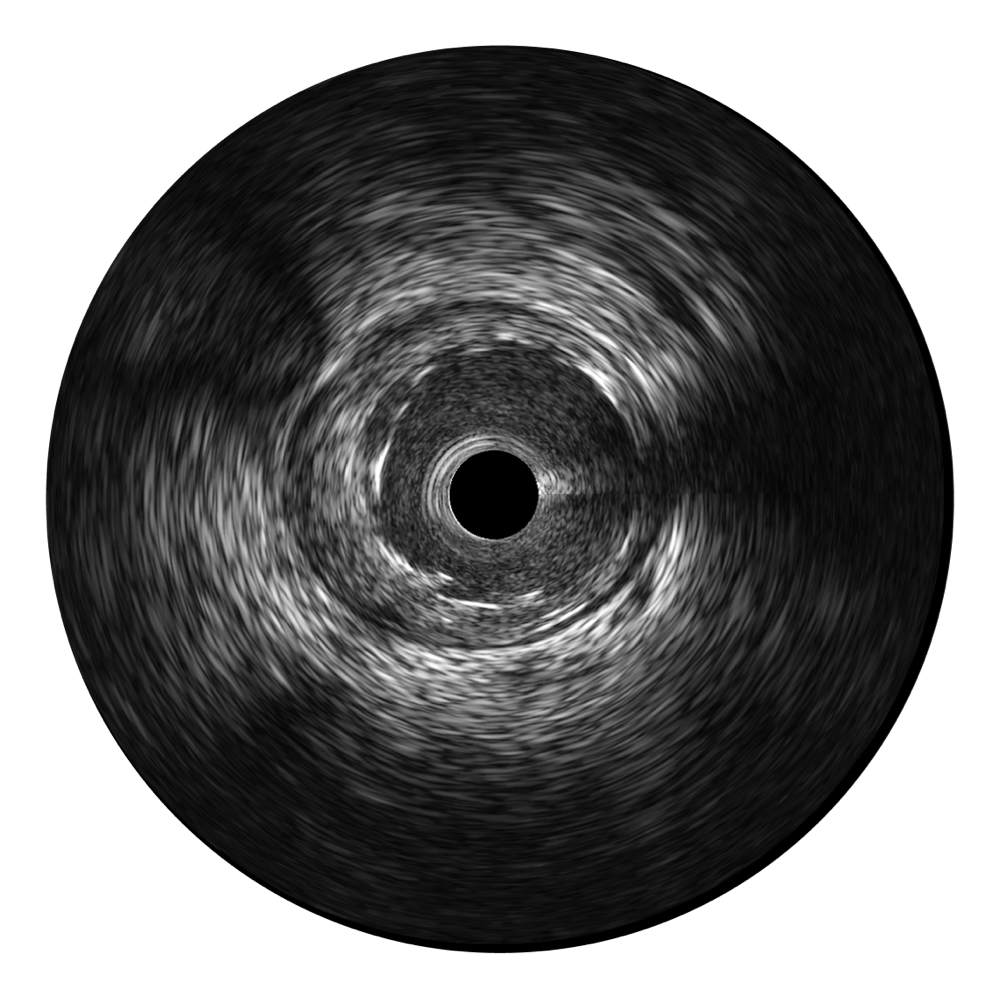

竞技宝(JJB)官方网站宽频IVUS图像

传统IVUS图像

对比传统IVUS导管成像,竞技宝(JJB)官方网站宽频IVUS图像的近场支架梁显影更细腻,远场中膜外血管仍清晰可辨,兼顾远中近,兼顾分辨力与穿透深度